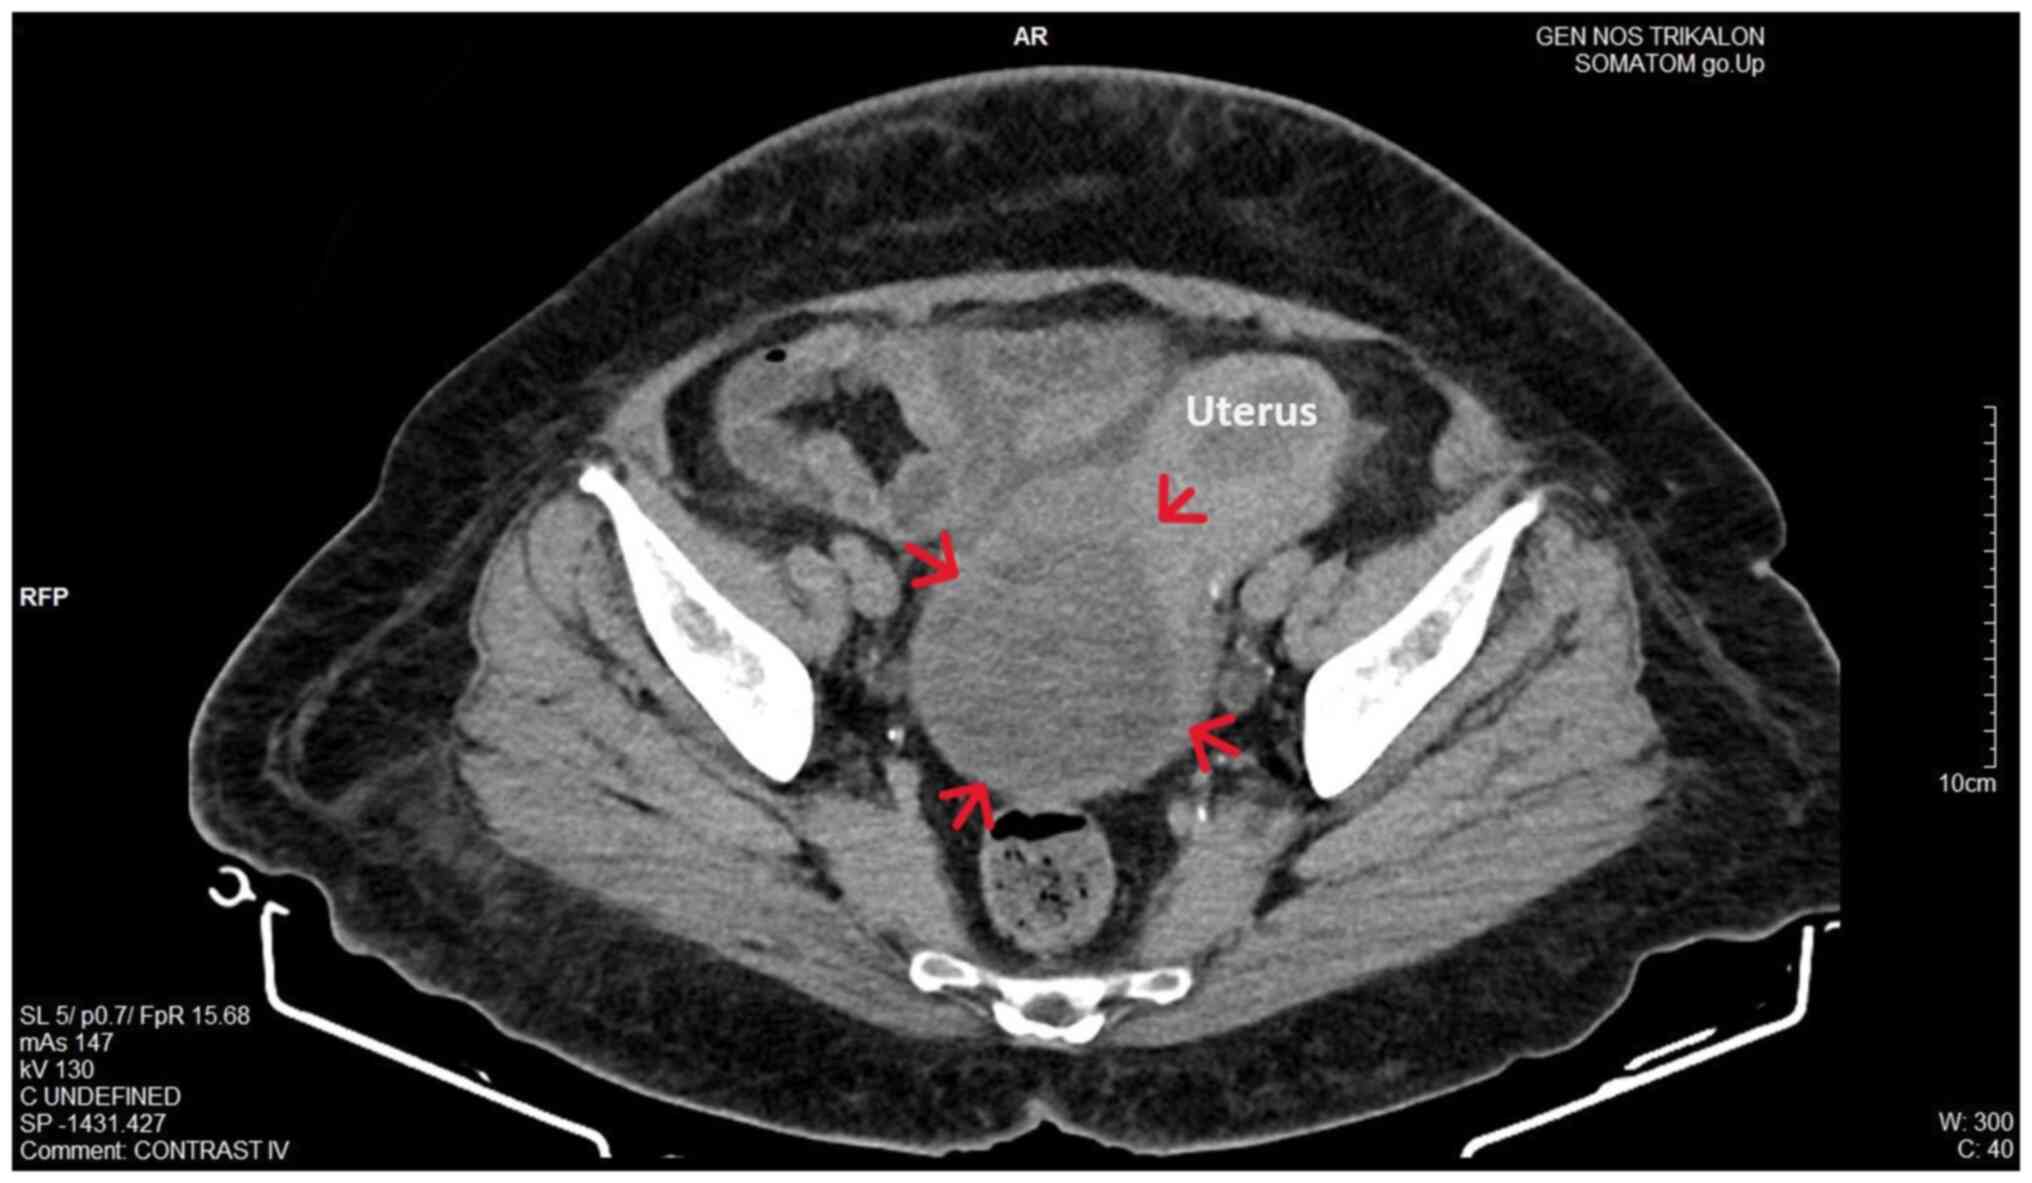

Upon a gynecological examination and upon the inspection of the vagina with a speculum, the cervix was not visible. In the upper third of the vagina, in the anatomical position of the cervix, a large solid mass was observed; the position of the external cervical os could not be clearly identified by visual inspection or palpation (Fig. 1). The transvaginal ultrasonographic findings were inconclusive. The scan detected the presence of a large well-circumscribed mass, with a maximum diameter of 10 cm, at the anatomical position of the cervix, raising suspicion of an intracervical leiomyoma (Fig. 2). A renal ultrasound revealed the bilateral dilatation of the pelvicalyceal system and the ipsilateral proximal ureter (Fig. 3). Furthermore, a computed tomography scan was performed, which revealed significant bladder dilatation and internal non-homogeneity of the cervical canal throughout its entire length, measuring 105x95x90 mm. This lesion caused the thinning of the external wall of the cervix and anterior displacement of the bladder. At the same time, it exerted compression on the posterior wall of the bladder, and malignancy arising from the cervix could not be excluded (Fig. 4). Additionally, computed tomography confirmed the dilatation of the pelvicalyceal system bilaterally up to the ureterovesical junction, accompanied by localized renal cortical thinning and lobulated contour of the left kidney. Magnetic resonance imaging was performed to further elucidate the findings of computed tomography. Magnetic resonance imaging revealed marked bladder distention with internal non-homogeneity of the cervical canal and the presence of a lobulated lesion that protruded intracanal with dimensions of 100x85x105 mm (Fig. 5). This finding was attributed to a large intracervical leiomyoma, strongly ruling out the possibility of cervical malignancy. The levels of tumor markers, namely carcinoembryonic antigen, cancer antigen 125, cancer antigen 15-3 and cancer antigen 19-9 were within the normal range.

Figure 4

Computed tomography imaging of a large prolapsed pedunculated submucosal uterine leiomyoma: Significant distention and non-homogeneity of the cervix (red arrows) with thinning of the external wall is depicted.